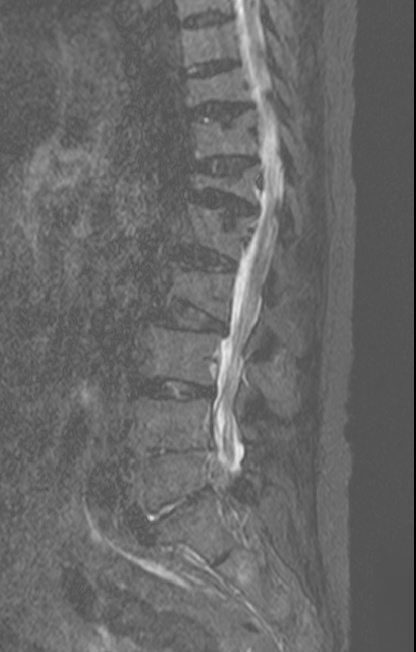

-L Spine MRI

- post L4-5 laminectomy

- flattening of T10 through L2 bodies with partially fatty bone marrow and some sclerotic change

- herniation of discs T10-11 through T12-L1 discs into adjacent vertebral bodies

- L2-3, L3-4 and L5-S1 diffuse bulging discs and ligamentum flavum thickening with indentation of thecal sac and encroachment on neural foramens

- some CSF effacement of L2-3 and L3-4 thecal sac

- partial to circumferential perineural fat effacement of left L5-S1 neural foramen

- decreased T2 signal intensity of discs with osteophytes

1. old T10 through L2 compression fracture with schmorl's nodes

2. L2-3, L3-4 and L5-S1 diffuse bulging discs

3. mild L2-3 and L3-4 central stenosis

4. moderate stenosis of left L5-S1 neural foramen

5. degenerative spondylosis